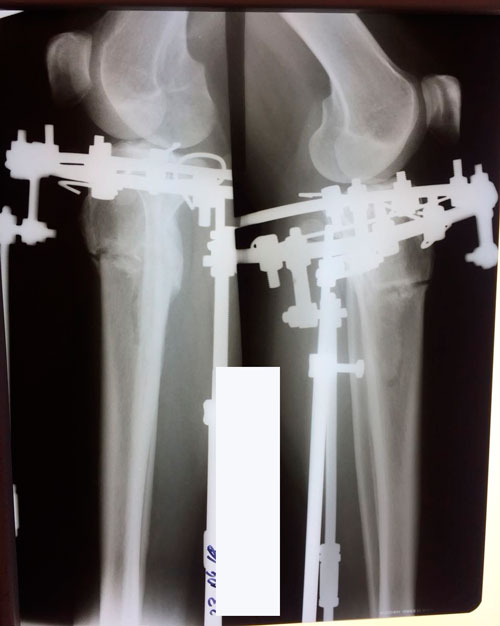

Дата операции 15.01.2018г.

Дата снятия аппаратов 23.04.2018г.

Срок лечения 97 дней.